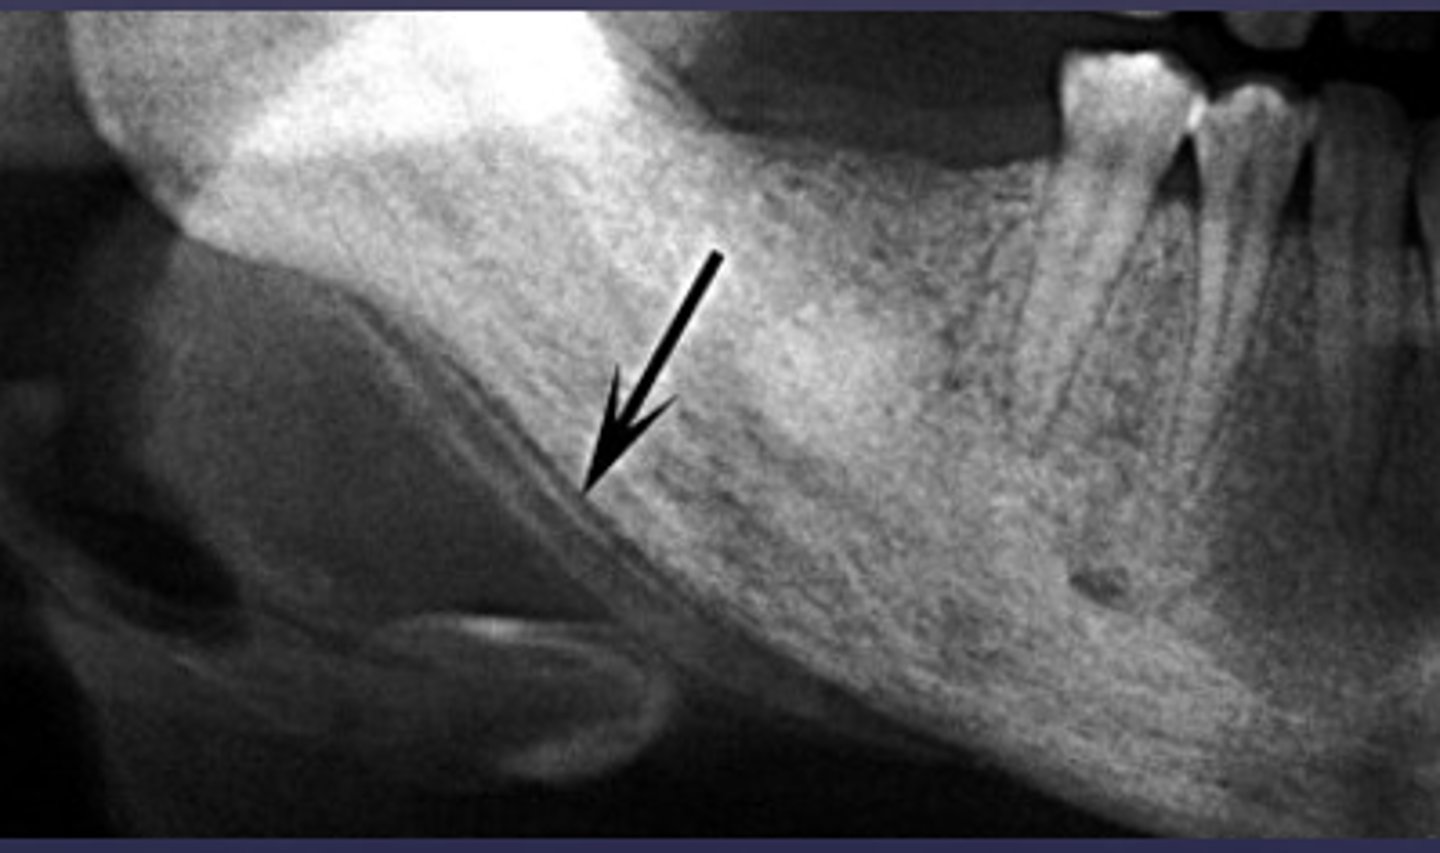

What is happening here?

periosteal reaction

Proliferative periostitis is also known as what?

onion skin

A radiograph of the mandible shows concentric layers of new bone formation parallel to the cortex, producing an "onion-skin" appearance. What is the diagnosis?

Periosteal reaction (acute osteomyelitis)

The "onion-skin" appearance seen in acute osteomyelitis results from which process?

Alternating cycles of periosteal bone deposition and resorption

How does early periosteal involvement in acute osteomyelitis form in relation to the cortex?

New bone formation parallel to the cortex